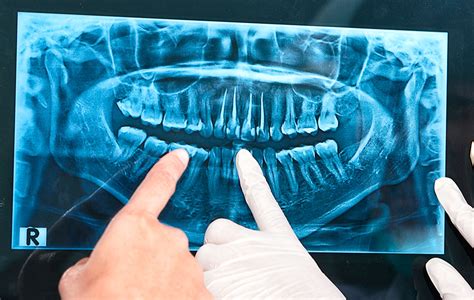

- Radiografías panorámicas: Ofrecen una vista general de todos los dientes, los maxilares y las estructuras circundantes.

Ventajas y aplicaciones de la radiografía panorámica: La radiografía panorámica es útil para evaluar el desarrollo dental, detectar quistes y tumores, y planificar tratamientos de ortodoncia e implantes.